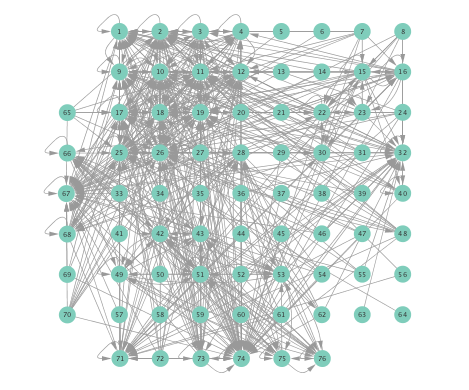

Figure 2 depicts networks inferred from different algorithms for both preictal and ictal intervals of the time series. The figure illustrates results obtained by the linear SVARM, and the K-SVARM approach with and without kernel selection. Each node in the network is representative of an electrode, and it is depicted as a circle, while the node arrangement is forced to remain consistent across the four visual representations. A cursory inspection of the visual maps reveals significant variations in connectivity patterns between ictal and preictal intervals for both models. Specifically, networks inferred via the K-SVARMs, reveal a global decrease in the number of links emanating from each node, while those inferred via the linear model depict increases and decreases in links connected to different nodes. Interestingly, the K-SVARM with kernel selection recovered most of the edges inferred by the linear and the K-SVARM using a polynomial kernel, which implies that both linear and nonlinear interactions may exist in brain networks. Clearly, one is unlikely to gain much insight only by visual inspection of the network topologies. To further analyze differences between inferred networks from both models, and to assess the potential benefits gained by adopting the novel scheme, several network topology metrics are computed and compared in the next subsection.